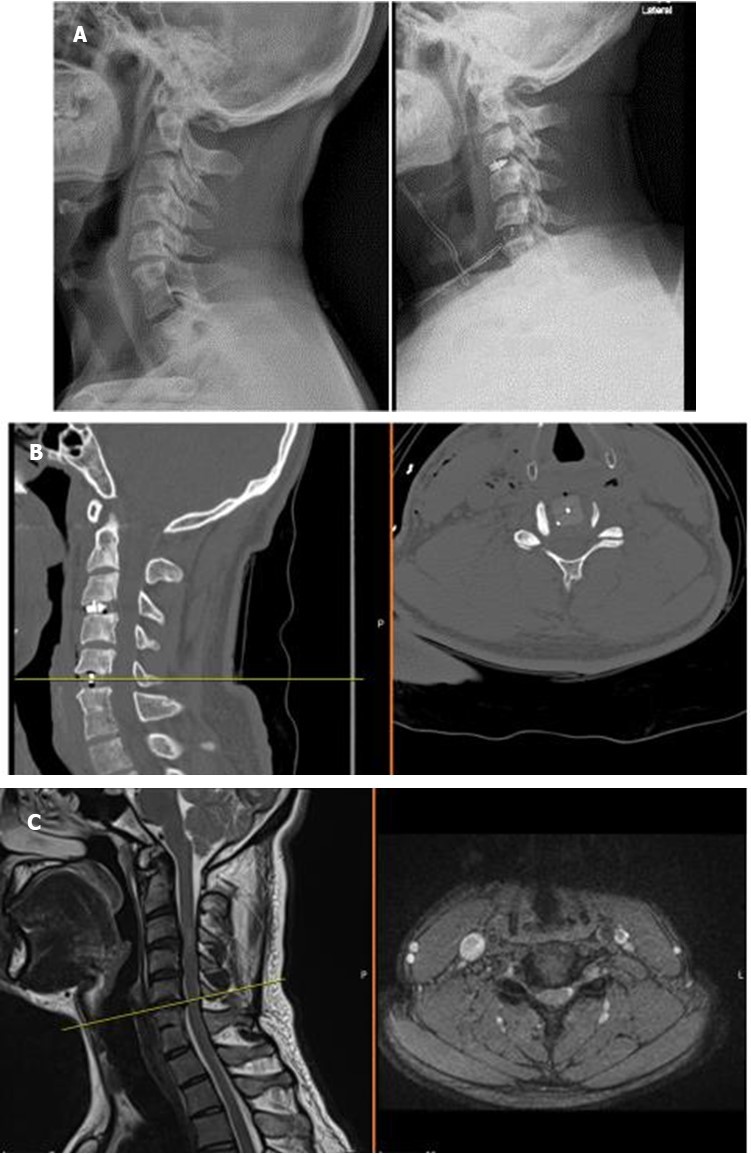

The operative technique was selected concerning our novel “Yilmaz-Yucesoy Classification System” (Table 3). Accordingly, 1 patient (4.54 %) had non-surgical treatment (Yilmaz-Yucesoy Grade 1), 6 patients (27.27 %) received anterior cervical arthroplasty (Yilmaz-Yucesoy Grade 2) (Figure 1), 7 cases (31.81 %) received anterior cervical discectomy or corpectomy and fusion with cervical cage and plate (Yilmaz-Yucesoy Grade 3) (Figure 2). These latter patients did not have cervical spinal instability but had spinal stenosis at more than 1 level. They needed at least 2 level discectomy or corpectomy due to the ossification of posterior longitudinal ligament or osteophyte formation. Eight patients (36.36 %) with cervical spinal instability were performed anterior cervical discectomy or corpectomy and fusion with cervical cage and plate (Yilmaz-Yucesoy Grade 4) (Figure 3).

Figure 1A, B, C.X-ray, computerized tomography, and magnetic resonance imaging views of a Yilmaz-Yucesoy Classification System Grade 2 patient.